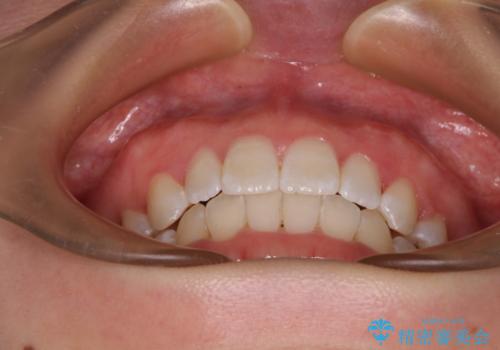

口元の突出感がない分、奥歯を前方に移動させる必要がありましたが、予定の2年間で無事に治療を終えることができました。